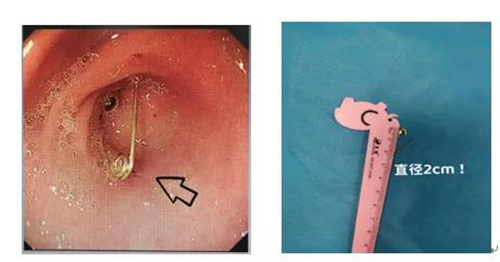

此時正值國慶節(jié)假期,內(nèi)鏡中心主任任悅義和消化科醫(yī)生王瑩瑩第一時間趕到醫(yī)院。根據(jù)X線攝片顯示異物位置及兒童消化道結(jié)構(gòu)特點,消化科和內(nèi)鏡中心團(tuán)隊制定了多種治療方案。在氣管插管全身麻醉后,消化科團(tuán)隊為患兒實施胃鏡檢查。醫(yī)生操作小兒細(xì)胃鏡進(jìn)入食管后,未發(fā)現(xiàn)有異物,繼續(xù)進(jìn)鏡發(fā)現(xiàn)別針已經(jīng)掉入胃內(nèi)幽門口附近,尖端扎入幽門口,萬幸未進(jìn)入腸道,孩子的食管粘膜及胃內(nèi)無明顯損傷及穿孔。根據(jù)術(shù)前制定的預(yù)案,消化科醫(yī)生先用異物鉗把別針“拖”到胃內(nèi),然后加上透明帽,防止損傷胃和食道粘膜,最后通過胃鏡把別針成功取出,手術(shù)過程不到5分鐘,寶寶轉(zhuǎn)危為安。